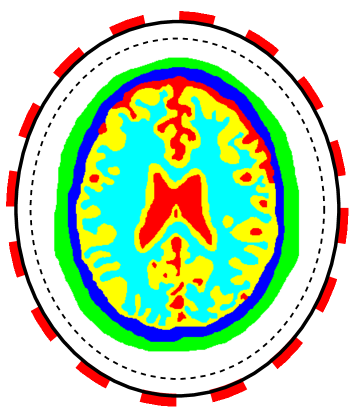

The first example is a heart-lung model [35], see Figure 1(a). The considered three tissues are heart (red, σ=0.7 S/m𝜎times0.7Sm\sigma=$0.7\text{\,}\mathrm{S}\mathrm{/}\mathrm{m}$), lung (cyan, σ=0.26 S/m𝜎times0.26Sm\sigma=$0.26\text{\,}\mathrm{S}\mathrm{/}\mathrm{m}$), and soft-tissues (blue, σ=0.33 S/m𝜎times0.33Sm\sigma=$0.33\text{\,}\mathrm{S}\mathrm{/}\mathrm{m}$). The model is placed into a circular region with a background material (white, σ=0.22 S/m𝜎times0.22Sm\sigma=$0.22\text{\,}\mathrm{S}\mathrm{/}\mathrm{m}$) and a radius r=25 cm𝑟times25cmr=$25\text{\,}\mathrm{c}\mathrm{m}$.

Figure 1: The 2D (a) heart-lung model and (b) human brain model embedded in a background material with electrodes (red squares) attached to the boundary (the solid black line). Different regions are marked with different colors. In (a), there are heart (red, σ=0.7 S/m𝜎times0.7Sm\sigma=$0.7\text{\,}\mathrm{S}\mathrm{/}\mathrm{m}$), lung (cyan, σ=0.26 S/m𝜎times0.26Sm\sigma=$0.26\text{\,}\mathrm{S}\mathrm{/}\mathrm{m}$), soft-tissues (blue, σ=0.33 S/m𝜎times0.33Sm\sigma=$0.33\text{\,}\mathrm{S}\mathrm{/}\mathrm{m}$), and background material (white, σ=0.22 S/m𝜎times0.22Sm\sigma=$0.22\text{\,}\mathrm{S}\mathrm{/}\mathrm{m}$). In (b), there are scalp (green, σ=0.5232 S/m𝜎times0.5232Sm\sigma=$0.5232\text{\,}\mathrm{S}\mathrm{/}\mathrm{m}$), skull (blue, σ=0.2923 S/m𝜎times0.2923Sm\sigma=$0.2923\text{\,}\mathrm{S}\mathrm{/}\mathrm{m}$), cerebro-spinal fluid (red, σ=2.1143 S/m𝜎times2.1143Sm\sigma=$2.1143\text{\,}\mathrm{S}\mathrm{/}\mathrm{m}$), gray matter (yellow, σ=0.5595 S/m𝜎times0.5595Sm\sigma=$0.5595\text{\,}\mathrm{S}\mathrm{/}\mathrm{m}$), white matter (cyan, σ=0.3240 S/m𝜎times0.3240Sm\sigma=$0.3240\text{\,}\mathrm{S}\mathrm{/}\mathrm{m}$) and the background mateiral (white, σ=0.4 S/m𝜎times0.4Sm\sigma=$0.4\text{\,}\mathrm{S}\mathrm{/}\mathrm{m}$). All electrodes are uniformly distributed with the same corresponding central section angle. It is assumed that the electrical conductivity σ𝜎\sigma in the region close to boundary (between solid and dashed black lines) is known.

The second example is the human brain model shown in Figure 1(b). The considered tissues in this model include scalp (green, σ=0.5232 S/m𝜎times0.5232Sm\sigma=$0.5232\text{\,}\mathrm{S}\mathrm{/}\mathrm{m}$), skull (blue, σ=0.2923 S/m𝜎times0.2923Sm\sigma=$0.2923\text{\,}\mathrm{S}\mathrm{/}\mathrm{m}$), cerebro-spinal fluid (red, σ=2.1143 S/m𝜎times2.1143Sm\sigma=$2.1143\text{\,}\mathrm{S}\mathrm{/}\mathrm{m}$), gray matter (yellow, σ=0.5595 S/m𝜎times0.5595Sm\sigma=$0.5595\text{\,}\mathrm{S}\mathrm{/}\mathrm{m}$) and white matter (cyan, σ=0.3240 S/m𝜎times0.3240Sm\sigma=$0.3240\text{\,}\mathrm{S}\mathrm{/}\mathrm{m}$). Refer to [5] for conductivities of different tissues. The shape of this model is close to an ellipse whose semi-major and semi-minor axes are 6 cmtimes6cm6\text{\,}\mathrm{c}\mathrm{m} and 7 cmtimes7cm7\text{\,}\mathrm{c}\mathrm{m}. The model is placed in an ellipse region with a background material (white, σ=0.4 S/m𝜎times0.4Sm\sigma=$0.4\text{\,}\mathrm{S}\mathrm{/}\mathrm{m}$). The semi-minor and semi-major axes of the region are 8 cmtimes8cm8\text{\,}\mathrm{c}\mathrm{m} and 9 cmtimes9cm9\text{\,}\mathrm{c}\mathrm{m}, respectively. The conductivity maps for the phantoms are piece-wise constant functions which will be mollified with

To work with CEM and LM-SCEM, 16 electrodes (red rectangles shown in Figure 1) are uniformly attached on the boundary (solid black lines). The section occupied by each electrode has the same central angle in both the heart-lung and human-brain models. The following computations assume that the conductivity in a small region close to boundary (between solid and dashed black lines) is known. The distance between the solid and dashed lines is given by δdsubscript𝛿𝑑\delta_{d}. This known region helps to improve the convergence of the algorithm. Three current patterns based on Fourier basis functions are used in the computations, which are Il(n)=cos(nθl)subscriptsuperscript𝐼𝑛𝑙𝑛subscript𝜃𝑙I^{(n)}_{l}=\cos(n\theta_{l}) for n=1,2,3𝑛123n=1,2,3, and θl=2πl/Lsubscript𝜃𝑙2𝜋𝑙𝐿\theta_{l}=2\pi l/L. The regularization parameter αksubscript𝛼𝑘\alpha_{k} is chosen to decrease exponentially, and αk=α0/aksubscript𝛼𝑘subscript𝛼0superscript𝑎𝑘\alpha_{k}={\alpha_{0}}/{a^{k}} with a>1𝑎1a>1. In what follows, a relatively large value is given to α0subscript𝛼0\alpha_{0}, and a value close to 1 is given to a𝑎a for a slow decreasing of αksubscript𝛼𝑘\alpha_{k} to ensure the convergence of the iterations.